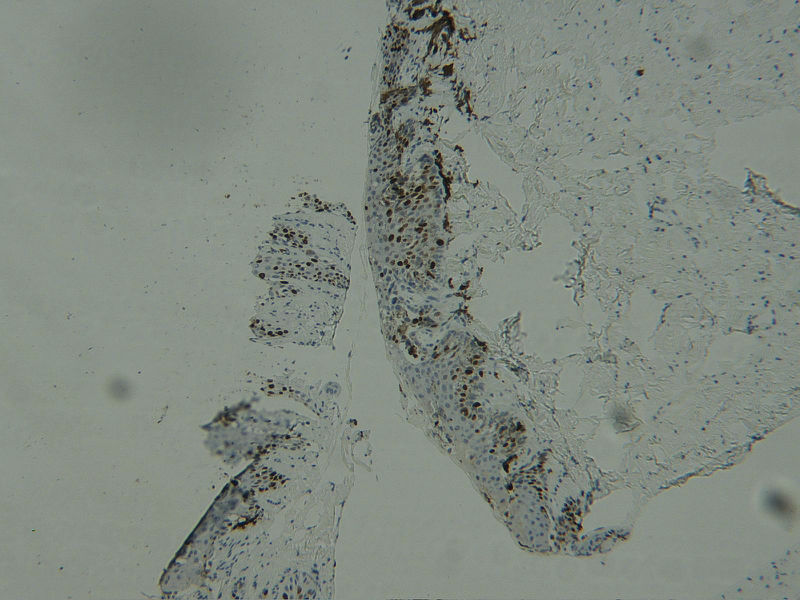

图2HMB45

女 68岁 右手拇指甲变黑及扩散2年,无自觉症状,有风湿性关节炎病史数年。